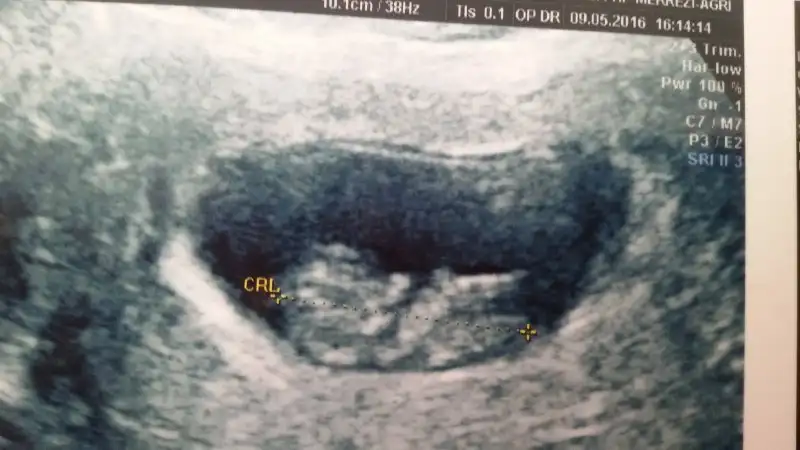

Sa benim yapılan tahmin turmustuBuda arkadaşımın görüntüsü yorum yağabilirseniz cok sevinirim .şimdiden cok tşk ederim

• image.webp

image.webp

10,4 KB · Görüntüleme: 149